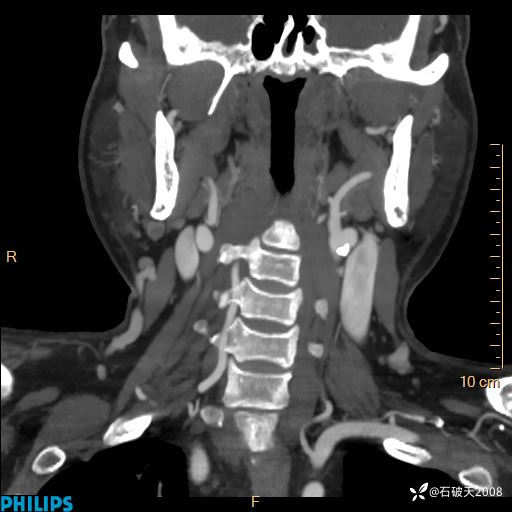

病例分享:颈部占位,一周后公布病理

男 57岁 主 诉:发现右侧颌下肿物1月余。

现病史:1月余前家属发现右侧颌下肿物。局部皮肤无红肿、热痛,无吞咽困难,无异物感,无恶心、呕吐,无头痛、头晕,无胸闷、胸痛,无发热、咳嗽、咳痰及呼吸困难。于我院行体表肿块彩超检查(2024.03.15我院)示:右侧耳下皮下软组织内低回声,未治疗。今为进一步治疗门诊以“腮腺肿瘤”为诊断收住我科,发病来患者神志清,精神可,饮食、睡眠及大小便正常,体重无明显下降。

MIP